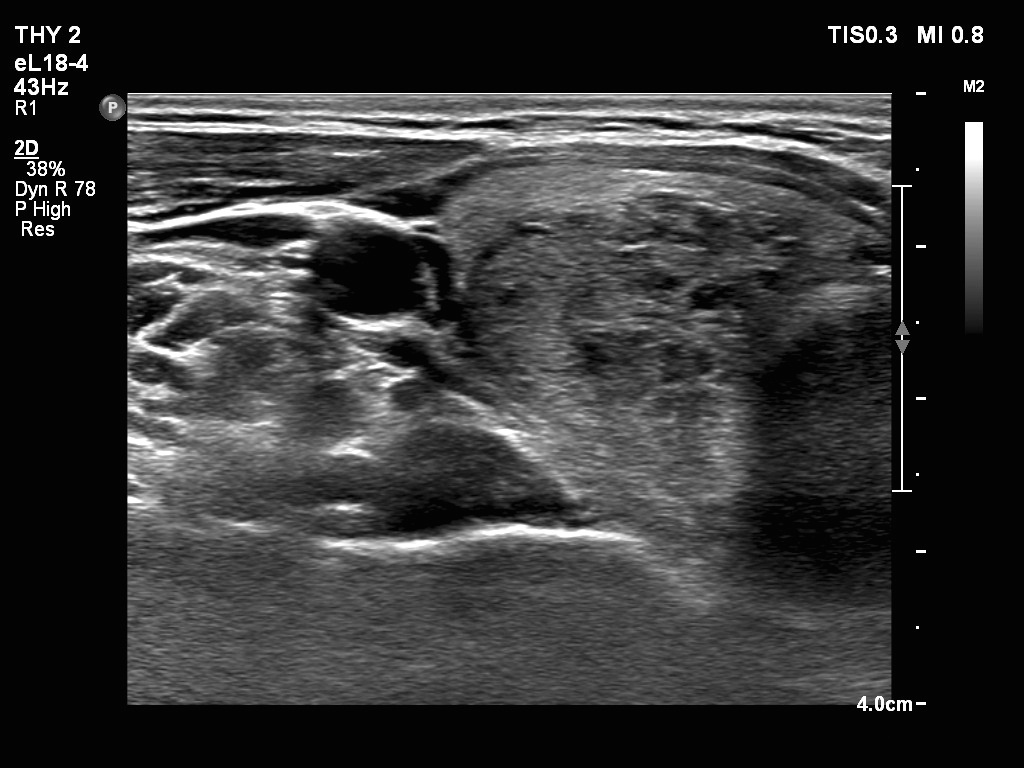

Ultrasonography. The thyroid was echonormal. There were two nodules in the right lobe. The upper was hyperechogenic-cystic while the lower was a minimally-moderately hypoechogenic. The latter had irregular, lobulated margins. There was a hypoechoic area in the upper two-third of left lobe. The discrete area presented ill-defined margins and decreased vascularization. A spongiform cyst was found in the lower pole of the left lobe.

Cytology of the nodule with irregular margins resulted in benign lesion, while cytology disclosed de Quervain's thyroiditis in the event of the hypoechoic area in the left lobe.